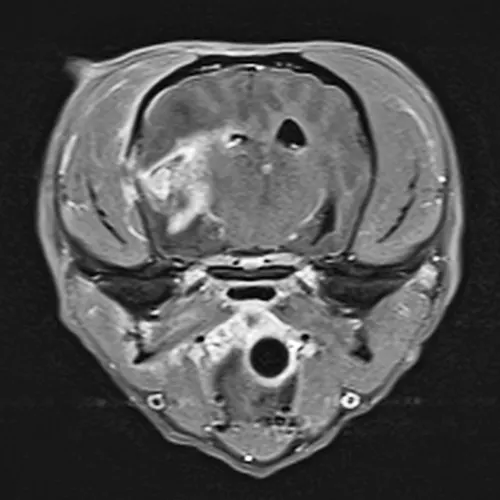

Figure 3

MRI of a patient with bilateral otitis media/interna. There is translocation of the infection across the bone invading the right side of the meninges.